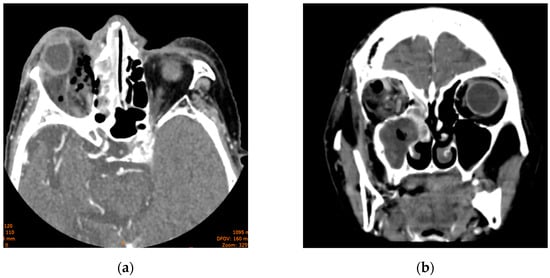

The head CT revealed right-sided orbital abscess with reticulation of the fat, pansinusitis with maxillary and ethmoid sinus opacification (Figure 2), multiple gas bubbles extending from the ethmoidal cells to the right orbit, a stretched right optic nerve, and posterior globe tenting (Figure 3). The abscess in the right canine space originated from the buccal roots of teeth 13 and 15. The fluid collection extended continuously from the right canine space upward and backward to the right lateral orbit.

Figure 2. Axial section of computed tomography scan displaying (a) maxillary sinus opacification and (b) ethmoid sinus opacification.